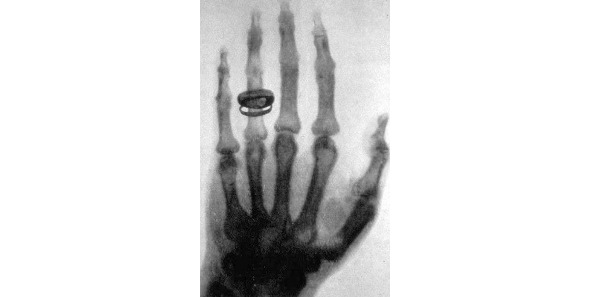

Рентгеноскопия

Главное открытие в своей жизни Конрад Рентген сделал 8 ноября 1895 года. Работая в своей лаборатории, он обратил внимание на то, что после включения тока в катодной трубке, почему-то начинает светиться покрытый слоем платиноцианистого бария бумажный экран. Причем происходило это вопреки «здравому смыслу», поскольку трубка была полностью закрыта плотным черным картоном, а значит, свет не мог проходить через него. Он выключил ток – свечение прекратилось, включил – экран снова засветился! И тогда он сделал вывод, что в трубке возникают икс-лучи, которые способны проходить через плотный материал, и заставляют флуоресцировать особые вещества. Причем в зависимости от вида материала и его толщины, преграда пропускала больше или меньше лучей. Как следствие, стало возможным анализировать структуру различных объектов. Установка, разработанная Рентгеном, выполняла совершенно новую функцию – неразрушающий анализ структуры непрозрачного объекта.

Рисунок 2. Первый рентгеновский снимок – рука Альберта фон Кёлликера, 21.01.1896 года